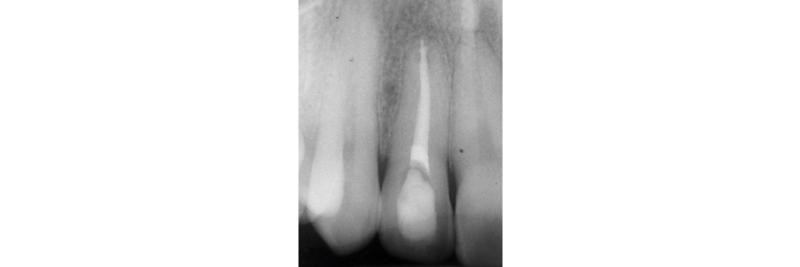

One treatment option that is often overlooked is internal non-vital tooth bleaching. This can be an excellent treatment option if the tooth has had RCT or needs RCT (Figs. 2A, 2B).

It must be stated that ample access preparation (Figs. 2A, 2B) is not required to internally bleach non-vital teeth, as a larger access preparation further compromises the tooth structurally. Figures 3A and 3B illustrate successful outcomes with a much more conservative approach (treatment by Dr. Steve Baerg, Gig Harbor, Washington).